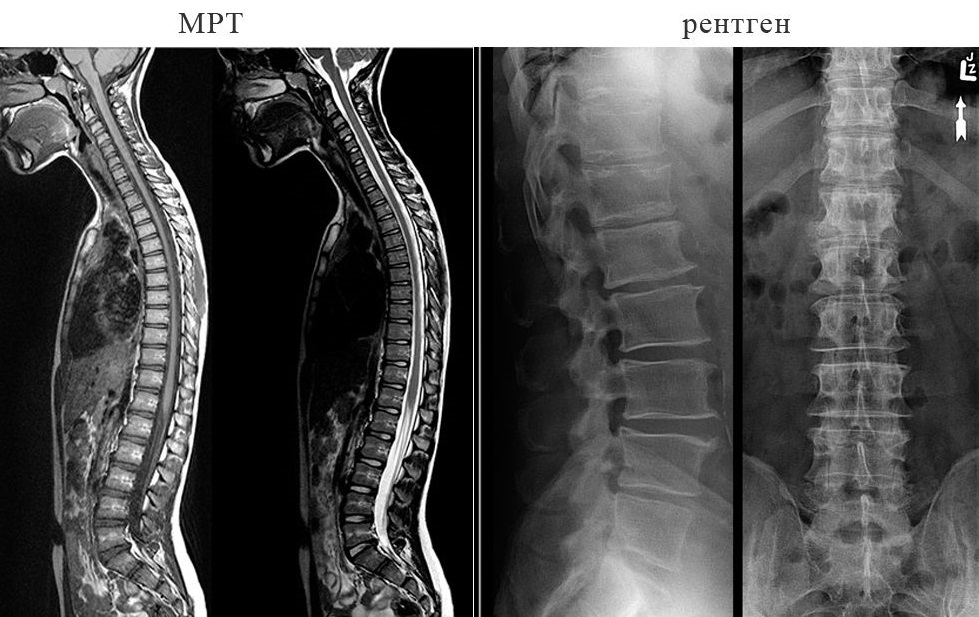

Рентгенография - позволяет выявить наличие искривлений, деформаций позвоночных структур и костных изменений.

Магнитно-резонансная томография (МРТ) необходима для детального изучения мягких тканей, выявления грыж, протрузий и воспалительных процессов.